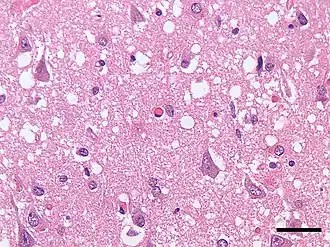

Болезнь Кре́йтцфельдта — Я́коба (или Болезнь Кройцфе́льдта — Я́коба; синонимы: псевдосклероз спастический, синдром кортико-стриоспинальной дегенерации, трансмиссивная спонгиоформная энцефалопатия, иногда ошибочно называемая «коровьим бешенством») — редкое прогрессирующее прионное нейродегенеративное заболевание коры большого мозга, базальных ганглиев и спинного мозга. Считается разновидностью губчатой энцефалопатии (группы заболеваний, вызываемых особыми инфекционными агентами — прионами). На сегодняшний день заболевание неизлечимо, летальный исход наступает в 100 % случаев[3]. Доступно только симптоматическое лечение, не влияющее на прогрессирование болезни. Диагностика заболевания затруднена из-за его редкости и отсутствия специфических симптомов.

- морфологическое и гистологическое исследование тканей головного мозга (коры, подкорковых ядер) при аутопсии (посмертная диагностика).